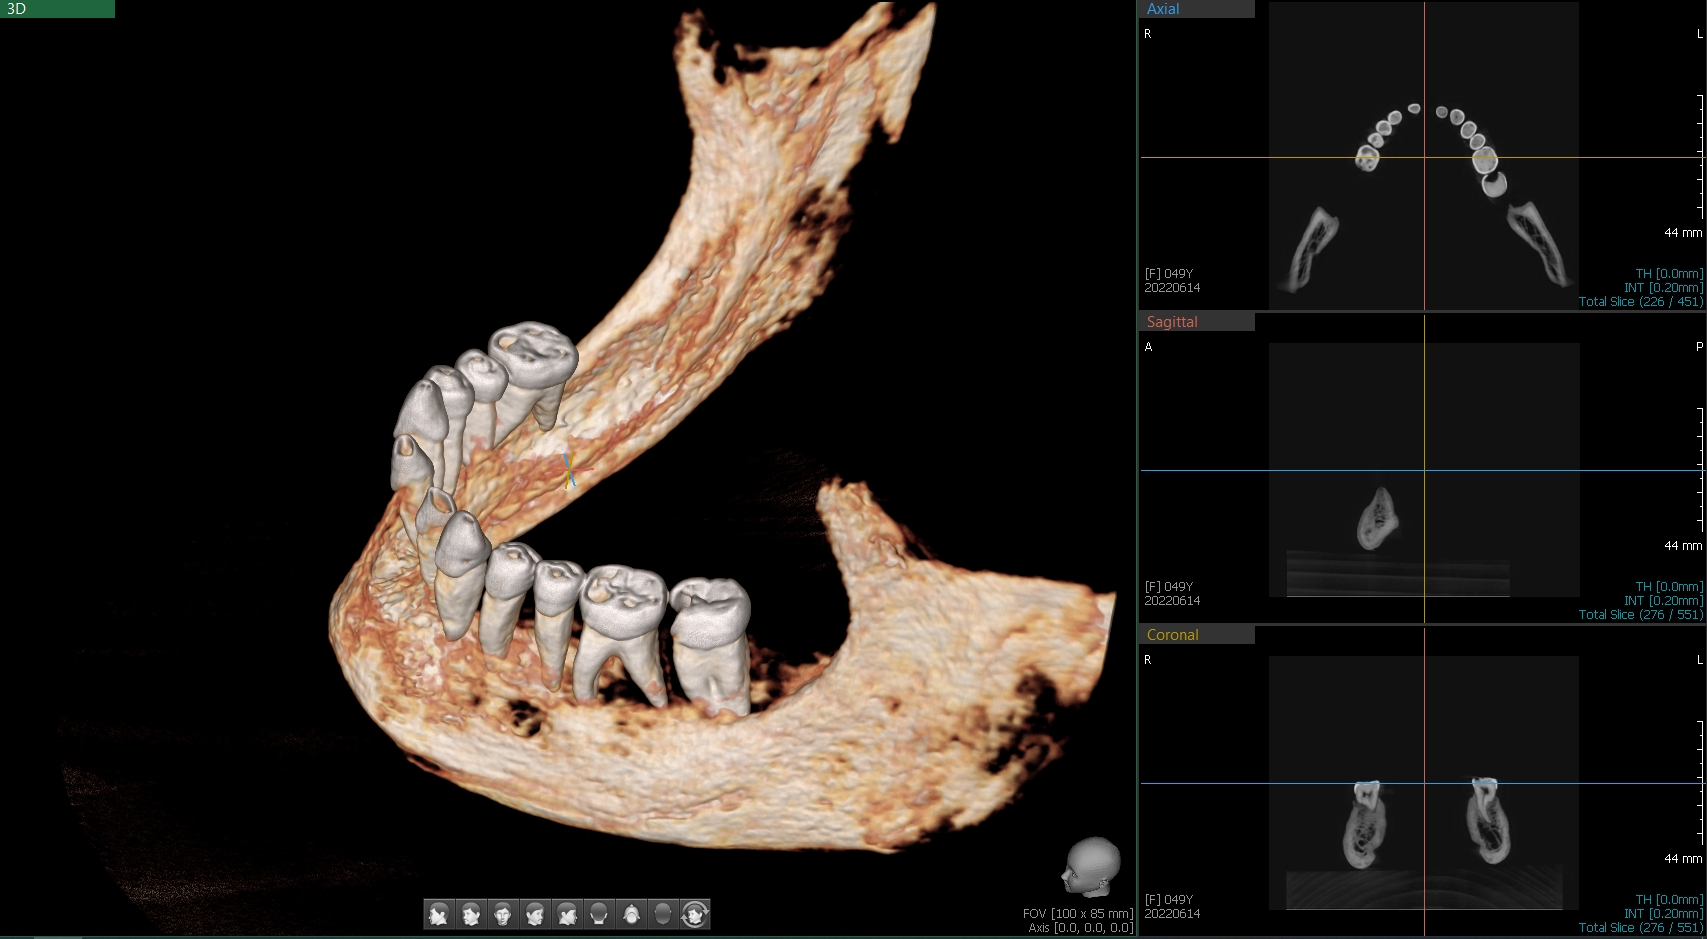

– Na przegląd stomatologiczny z Muzeum w Gliwicach zostało przekazanych 6 czaszek lub ich części, z czego 5 należało do osób dorosłych, a jedna do młodego dorosłego. Wykonaliśmy podstawowy przegląd, badanie pod kątem próchnicy (DiagnoCam), wybrane zęby były oceniane pod mikroskopem, pobrano również skany 3D i przeprowadzono cyfrową diagnostykę radiologiczną. Każdy z „pacjentów” miał założoną typową kartotekę, w której zaznaczano spostrzeżenia dentystów. Całość trwała 3 intensywne dni, a po tym czasie eksponaty wróciły do Muzeum – opisuje przebieg badań lek. dent. Marta Szymańska-Pawelec, dentystka odpowiedzialna za projekt z Dentim Clinic Medicover w Katowicach.

– Na podstawie diagnostyki radiologicznej można wnioskować, że wskutek nieleczonej próchnicy u jednego z pacjentów powstała zmiana torbielowata przy korzeniu zęba trzonowego. Osoba ta nie mogła widocznie liczyć na żadną pomoc chociażby cyrulika, więc pozostawiony, zainfekowany korzeń spowodował destrukcję ograniczeń kostnych i przewlekły stan zapalny błony śluzowej zatoki szczękowej – opisuje dentysta.

I, jak dodaje dentystka, warte odnotowania jest ponadnormatywne starcie zębów: – Zęby niektórych osób były bardzo starte, aż widoczne były odsłonięta zębina i miazga. Wynikać to może z charakteru spożywanych produktów, które były twarde, włókniste, a w chlebie mogły znajdować się okruchy kamienia z młyna. Obecnie starcie zębów przypisujemy stresowi, który wyzwala często nieświadome zgrzytanie zębami. Czy wtedy tak bardzo też się stresowano? Pewnie tak, choć powody były zupełnie inne.

– W jednym przypadku zaobserwowaliśmy cechy przewlekłego zapalenia przyzębia, co skutkowało zanikiem kości części zębodołowej żuchwy z tzw. obnażeniem furkacji korzeni. To znaczy, w uproszczeniu, że tkanki były tak nisko aż dostrzegalne były nawet korzenie zębów trzonowych. Z tego powodu osoba ta, za życia, mogła już wcześniej utracić zęby, bo miejsca po brakach były zagojone – opisuje chirurg z Dentim Clinic Medicover.

Zęby w 3D

Cyfrowe skany 3D też dostarczyły wielu ciekawych informacji, bo okazuje się, że przynajmniej jeden aspekt zdrowia zębów raczej nie przysparzał im zmartwień – zgryz.

– Raczej nie musieli chodzić do ortodonty. W tych przypadkach, w których mieliśmy taką możliwość, czyli były zachowane szczęka i żuchwa, stwierdzaliśmy prawidłowe warunki zgryzowe (zgryz eugnatyczny). To również może być zasługą diety. Żucie i gryzienie twardych, włóknistych produktów sprzyja prawidłowemu rozwojowi kości szczęki oraz żuchwy, a tym samym właściwemu ustawieniu się zębów. Nie bez znaczenia może być też fakt braku smoczków dla dzieci, które – zbyt długo używane – sprzyjają wadom zgryzu. Dzieci wtedy karmiono piersią, a dieta nie zawierała aż tylu miękkich, papkowatych produktów – zauważa ekspertka.